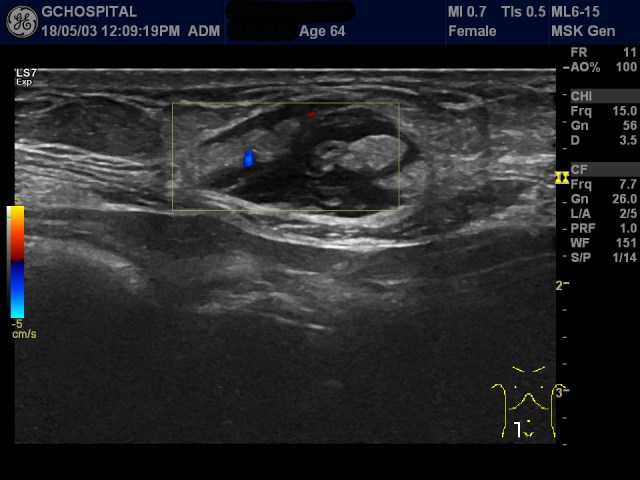

우측 유방 외에 우측 액와부위도 비슷한 모양과 에코음영의 종괴가 보입니다. 마찬가지로, 컬러도플러영상에서 뚜렷한 신호는 보이지 않습니다.

주로 피하지방층 및 intra-mammary fat 층에 다발성으로 발생하며, 컬러도플러영상에서 신호가 보이지 않는 병변으로 감별할만한 질환들은 myofibroblast cell infiltrations, multifocal panniculitis, metastases등이 있습니다.

이 환자는 우측유방의 종괴를 떼어내서 조직검사를 한 결과 malignant lymphoma로 진단되었습니다.

통상적으로 악성 림프종은 대게 컬러도플러영상에서 매우 혈관이 풍부하기 때문에 도플러영상이 매우 중요하며, hypervascular, well-circumbscribed mass가 특징적인 초음파영상소견으로 알려져 있습니다. 그런데, 이번 사례는 컬러도플러영상에서 vascularity가 확인되지 않아 진단이 쉽지 않았던 경우입니다.

앞으로도 피하지방층에 다발성의 종괴가 이와 비슷한 양상을 보이면, 컬러도플러영상에서 혈관신호가 보이지 않더라도 악성 림프종의 가능성을 배제하지 않도록 주의해야겠습니다.